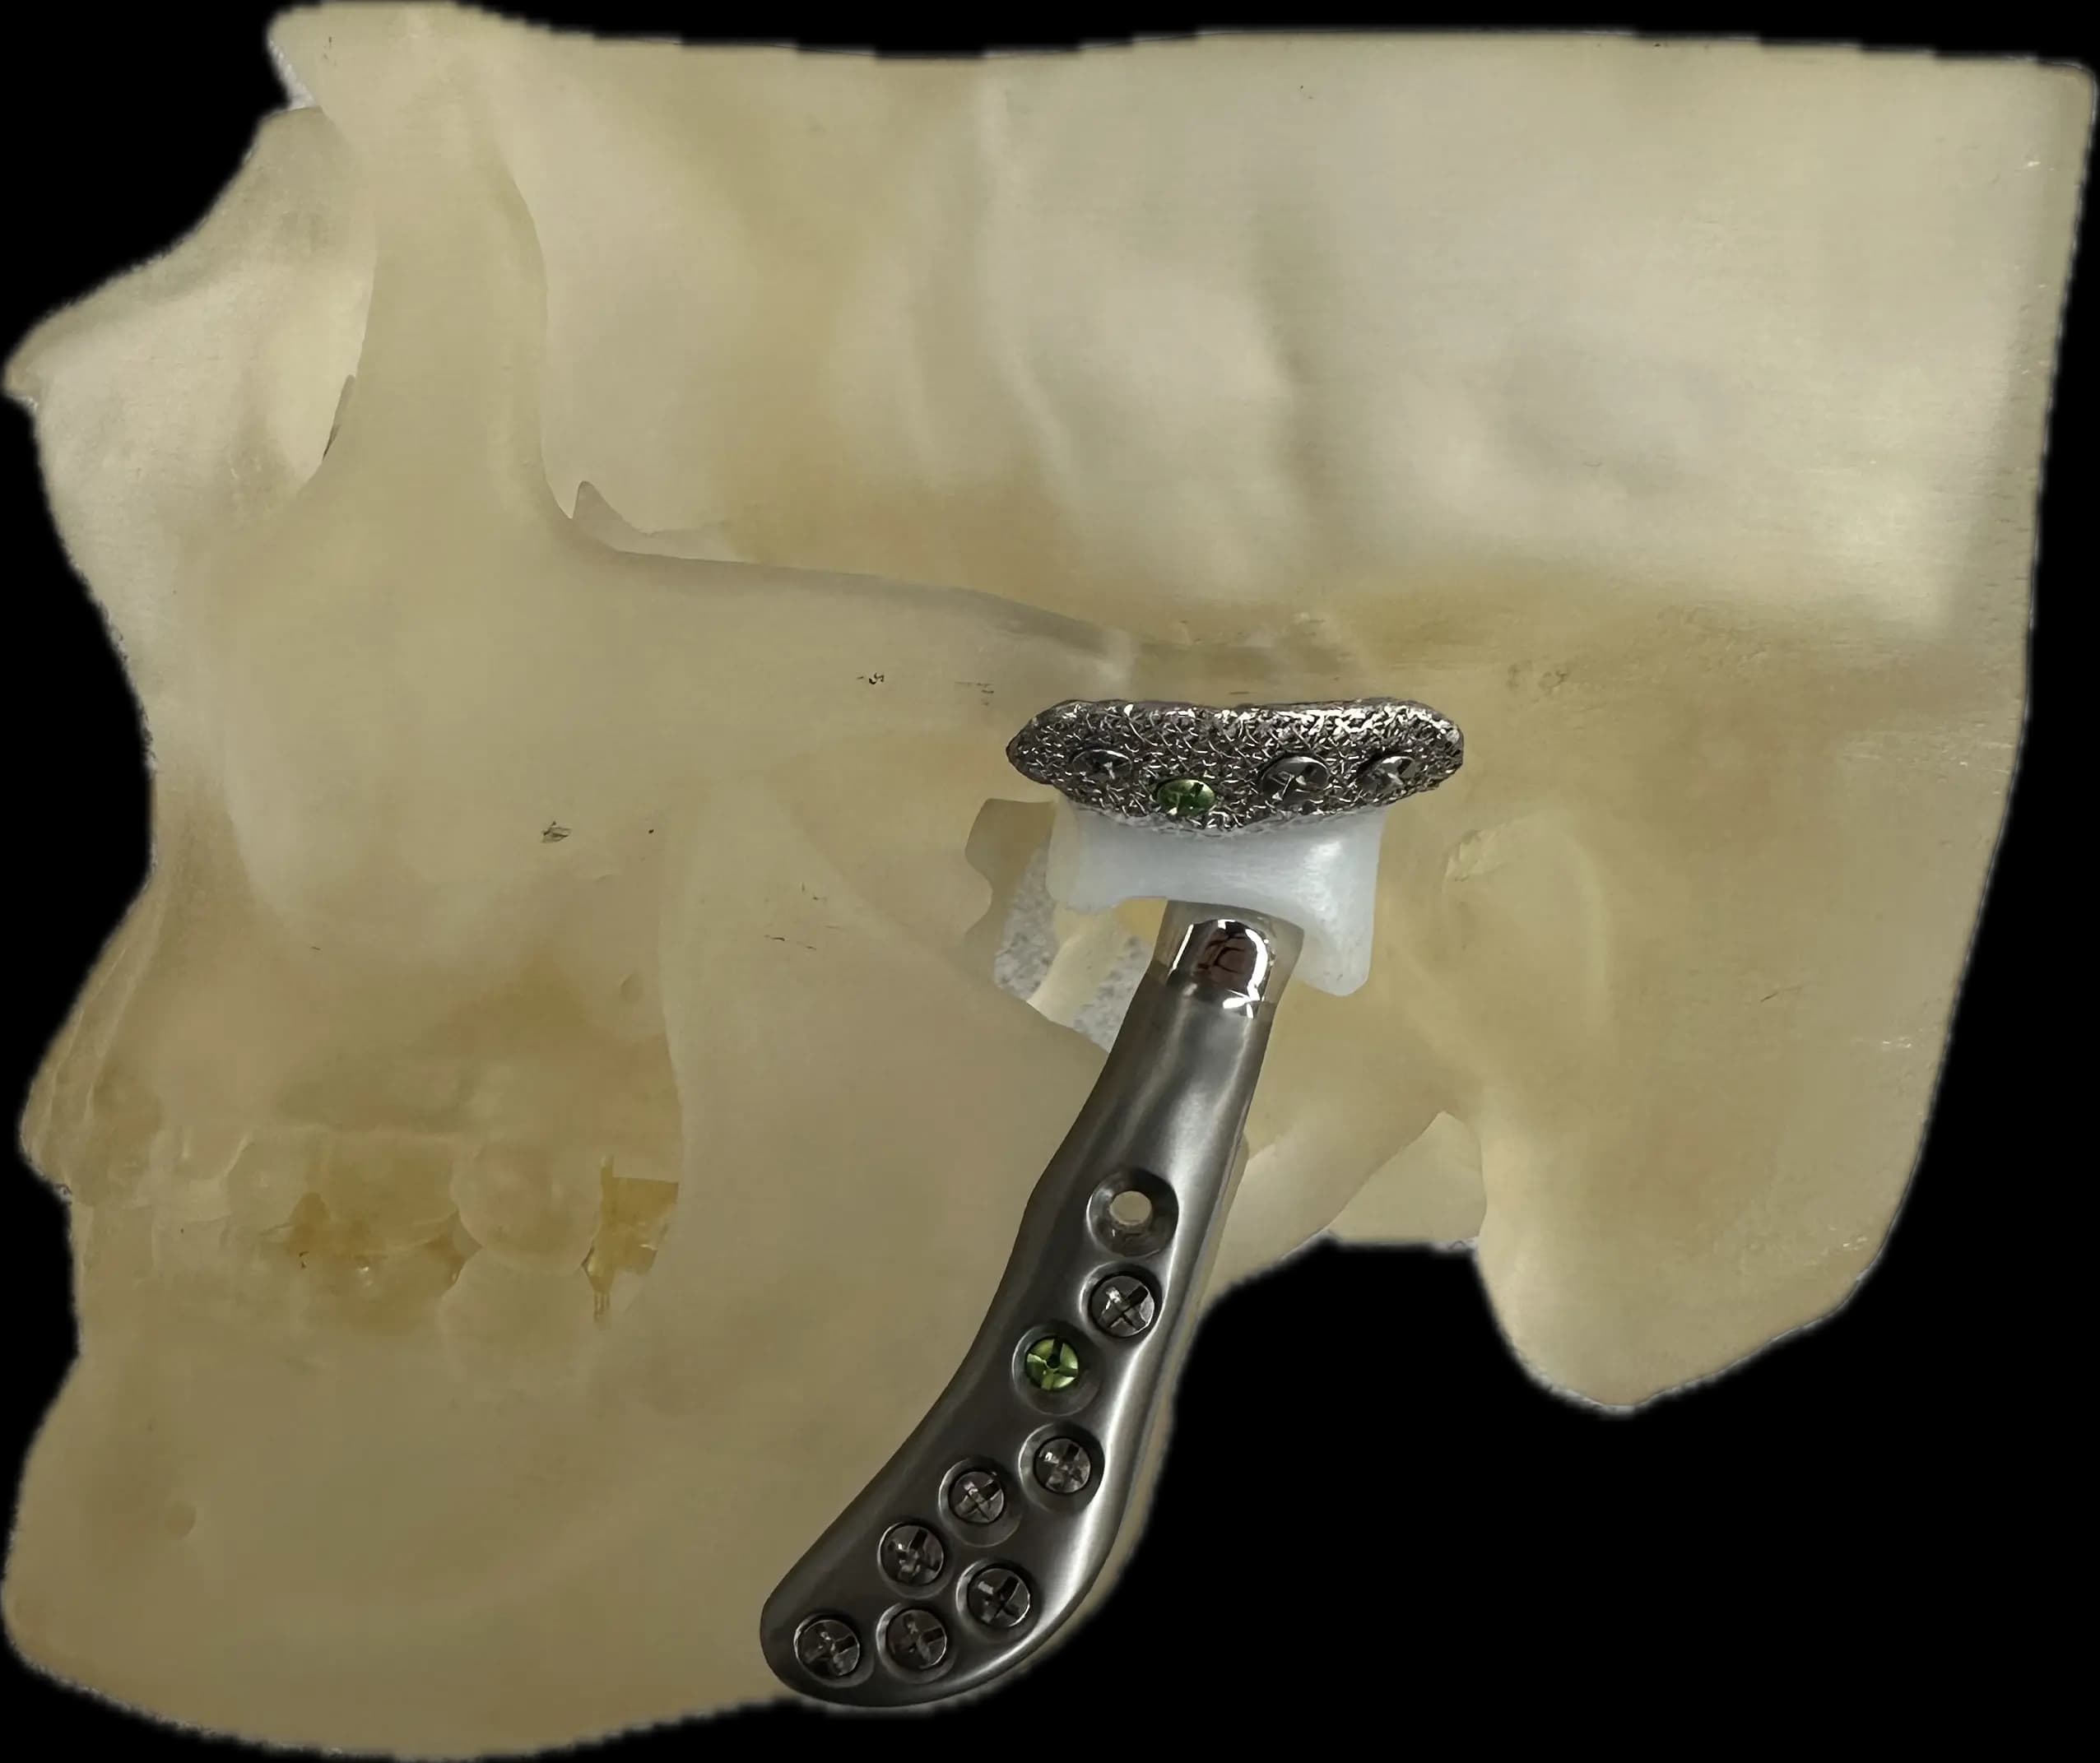

Joint Replacements